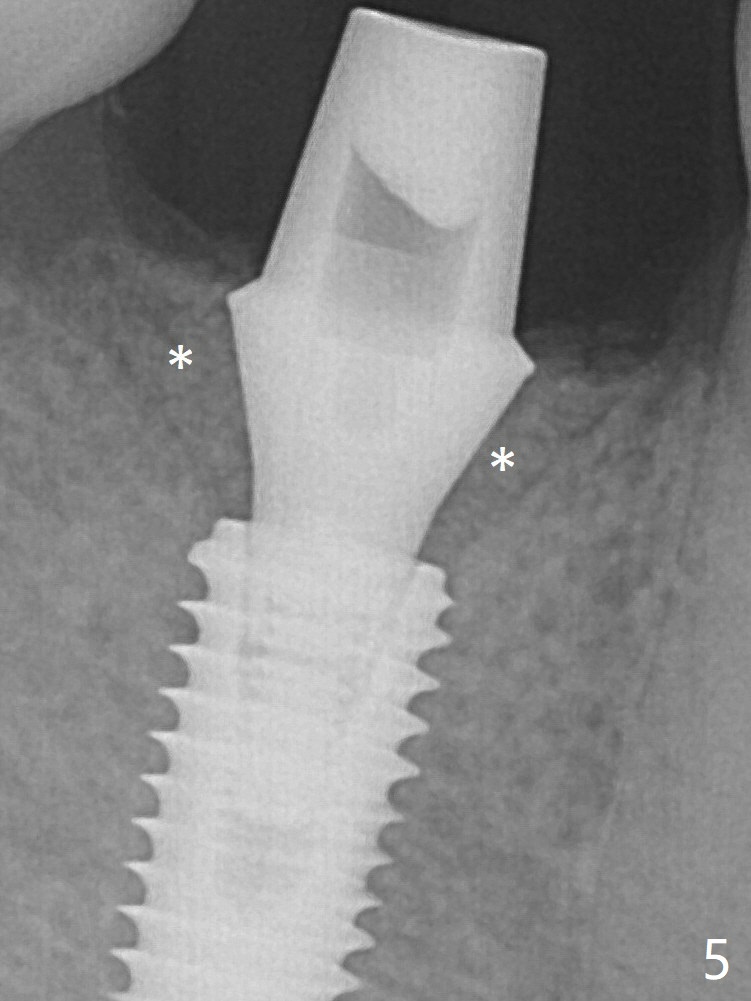

After insertion of a 5.7x5.5(3) mm abutment, Vanilla Graft is placed (Fig.5 * with 2 mm buccal gap). The abutment with a provisional is loose 4 months postop (Fig.6). The abutment screw is loose and fractured 8 and 11 months post cementation, respectively (Fig.7). The fractured screw seems to be loose within the implant well and is easily re-winded out. When the crown/abutment is loose 2nd time 1 year 7 months post cementation (Fig.8 taken post retightening), the screw at #19 fractures. The tooth #2 needs a crown. The patient cannot use the anterior teeth, since the teeth #8 and 9 have root fracture. Can extraction and bone graft increase bone height? The screw re-fractures 9 months later (Fig.9).